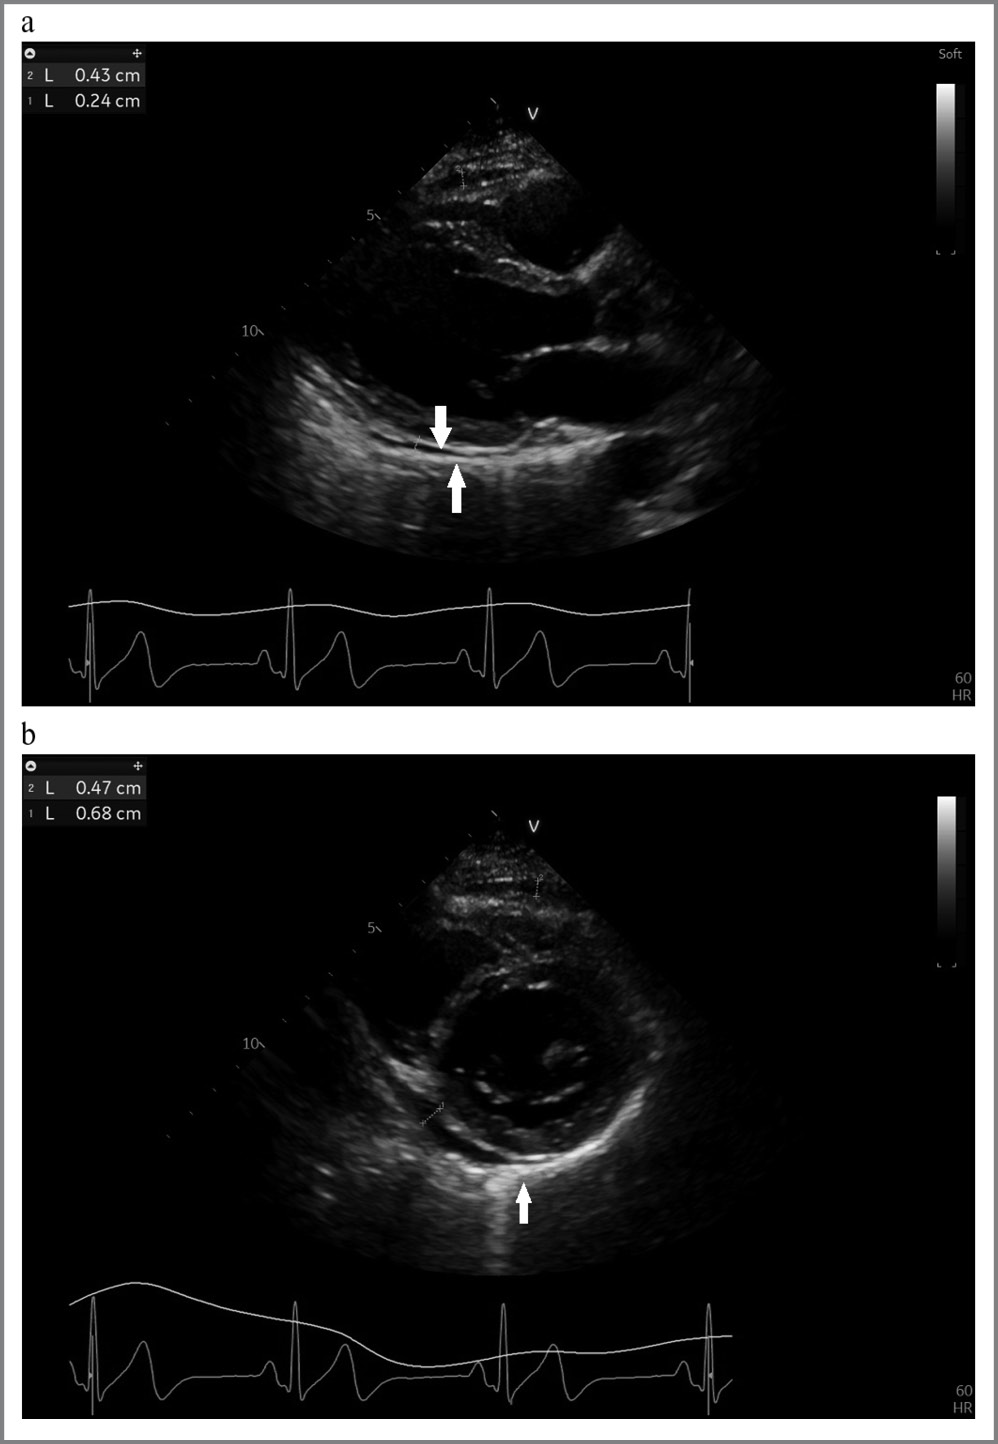

По данным трансторакальной ЭхоКГ: регистрировалась сепарация листков перикарда в области атриовентрикулярной борозды, по переднебоковым стенкам правых камер – до 5–6 мм. Объем жидкости составлял приблизительно 200 мл. ФВ – 60%, зон нарушения локальной сократимости нет (рис. 6, a, b).

Рис. 6. Результаты ЭхоКГ пациентки С.: a – парастернальная проекция по длинной оси ЛЖ, жидкость по задней стенке ЛЖ; b – апикальная позиция по короткой оси ЛЖ, гиперэхогенность листков перикарда.

Fig. 6. Patient C’s echocardiogram results: a – parasternal view along the long axis of the LV, fluid along the posterior wall of the LV; b – apical position along the short axis of the LV, hyperechogenicity of the pericardial layers.